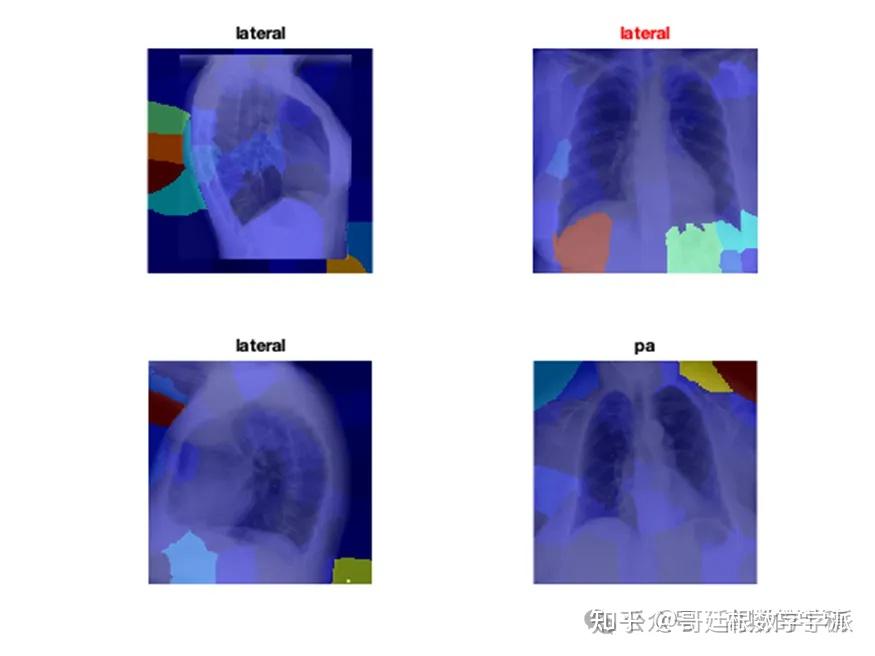

医学图像的深度学习可解释性(MATLAB R2021B)